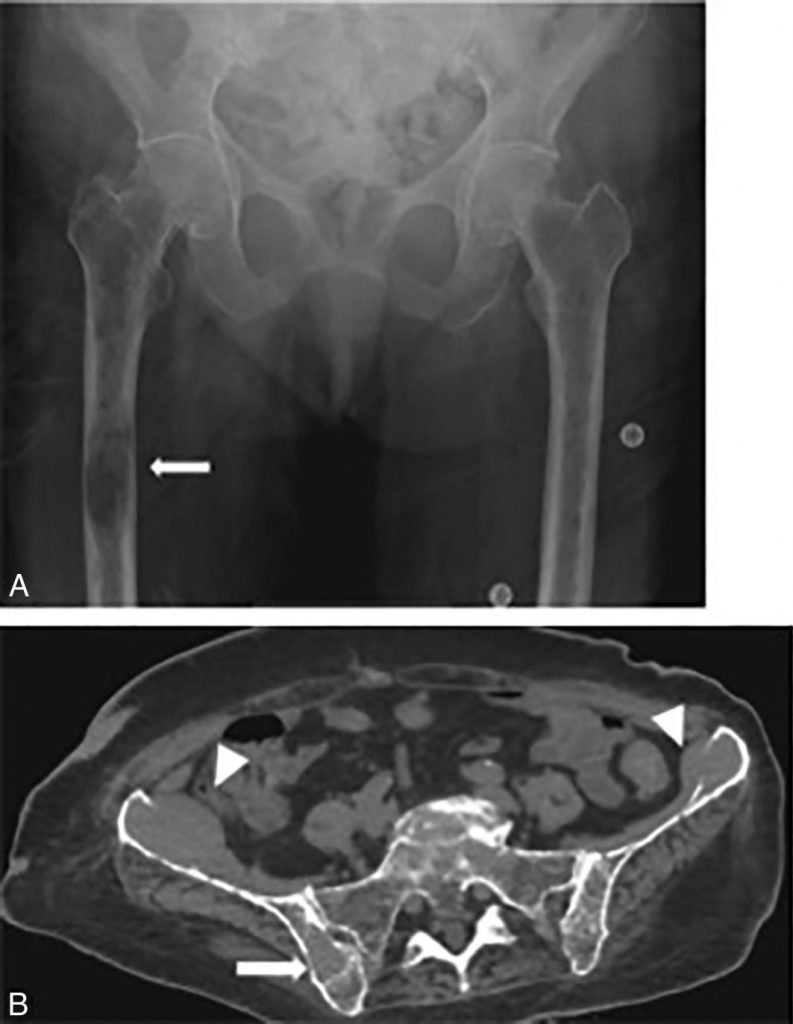

Fig. 80.1 Radiographie du bassin et du fémur de face (A) et scanner en coupes axiales du bassin (B) d’un patient atteint d’un myélome multiple.

Sur la radiographie, il existe de multiples petites lacunes ainsi qu’une volumineuse lésion lytique non cerclée (flèche). Sur le scanner, la graisse médullaire est remplacée par l’infiltration tumorale (flèche), avec par endroits une lyse de la corticale, sans aucune reconstruction, due à l’infiltration tissulaire qui bombe dans les parties molles.

Les images caractéristiques sont des lacunes à l’emporte-pièce : lésions lytiques à bords nets sans condensation périphérique, souvent multiples (cf. figure 80.1A).

Les images caractéristiques sont des lyses des corticales et des travées osseuses, souvent multiples, sans condensation périphérique, au sein desquelles la graisse médullaire osseuse est remplacée par des lésions de densité tissulaire (à peu près égale à celle du muscle) (cf. figure 80.1B).